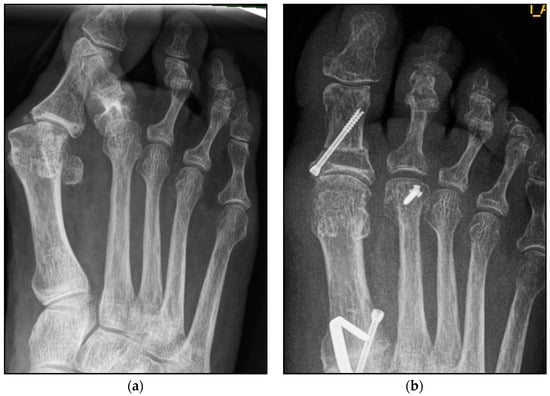

Figure 5.

Pre- and postoperative radiographic results of combined hallux valgus surgery and Weil osteotomy of metatarsal 2 and 3 (group B without screw), right foot. (a) Weight-bearing radiograph: anteroposterior view preoperative, (b) weight-bearing radiograph: anteroposterior view, 3 months postoperative.

We collected the following data from the weight-bearing dorsoplantar foot radiographs after a mean follow-up period of 16 weeks (3.6 months). With no significant difference between groups, the mean MTP angle changed from 9.24° to 12.99° preoperative to postoperative (medial deviation: −n, lateral deviation: +n). As can be seen from the mean SEM in Table 2 and Figure 4 and Figure 5, the maximum medial and lateral deviations from pre- to postoperative were significantly different. The mean MTP only changed from 9.3 to 12.9 and was in the range of a mild lateral deviation. This was also observed equally in both groups (p > 0.05). Of note, the postoperative visibility of the joint space was documented significantly more often in the group without screw fixation; this means the space between the subchondral bone of the metatarsal and the toe was seen without overlay (p < 0.05).

The underlying assumption of our study and the knowledge gained from our results can be further elaborated upon. An inharmonious transverse plane alignment can also be corrected with Weil osteotomy and does not require osteosynthetic fixation of the displaced metatarsal head [24]. The results confirm, based on postoperative weight-bearing radiographs, that the surgically induced correction is maintained regardless of screw fixation. An objectifiable criterion was the metatarsophalangeal angle measured pre- and postoperatively using weight-bearing radiographs in the dorsoplantar view (Figure 1 and Figure 2). In both treatment groups, it was possible to bring the maximum axis deviation closer to the mean value; the mean difference between pre- and postoperative metatarsophalangeal angle was only 3.8°. On average, 10.6 degrees were required to achieve the desired surgical result, regardless of screw fixation (Figure 4 and Figure 5). However, the significantly higher possibility of viewing the affected metatarsal joint space postoperatively can also be considered a successful outcome of the restoration without screw fixation. The visibility of the articular surface, in turn, proves the centering of the metatarsal head in the transverse plane as well as a sufficient correction in the sagittal plane (Figure 6 and Figure 7) [25]. Again, the inability to view the joint space indicates that inadequate correction of the claw toe deformity as well as the metatarsal, which was considered “too long”, was performed [1,14,26].